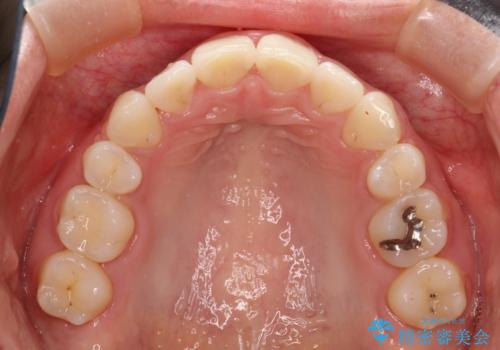

抜歯をして矯正をすることで、前歯を後方に移動させ、ガタガタを改善することができました。